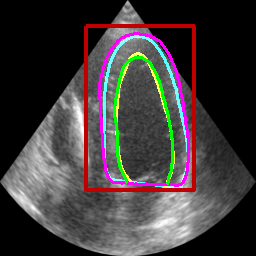

Table II displays the segmentation accuracy computed on the full dataset from patients having good and medium image quality ( patients) for the 4 algorithms described in section Sec. IV-D. Mean and standard deviation values for each metric were obtained from cross-validation on the 10 folds of the dataset. The values in bold correspond to the best scores for each metric. From these results, one can see that all the attention-based networks produced either the same, or better results than the baseline U-Net1, with AG-U-Net and LU-Net being the best performing models. Indeed, AG-U-Net obtained the overall best results for the segmentation of the LVEndo border ( value of mm and value of mm), leading to segmentation scores close but still higher than the intra-observer variability for this structure. The LU-Net-m5 approach obtained the best results for the segmentation of the LVEpi border ( value of mm and value of mm) and the lowest number of geometric outliers (%). Interestingly, these scores are either equivalent or lower than the intra-observer variability for this structure. It is also worth noting the robustness of the LU-Net model with respect to the choice of margin parameter, as margins of % and produce almost the same segmentation scores for all metrics. An illustration of the segmentation performance of the LU-Net-m5 network compared to the baseline U-Net1 model on three different cases is provided in Fig. 2.